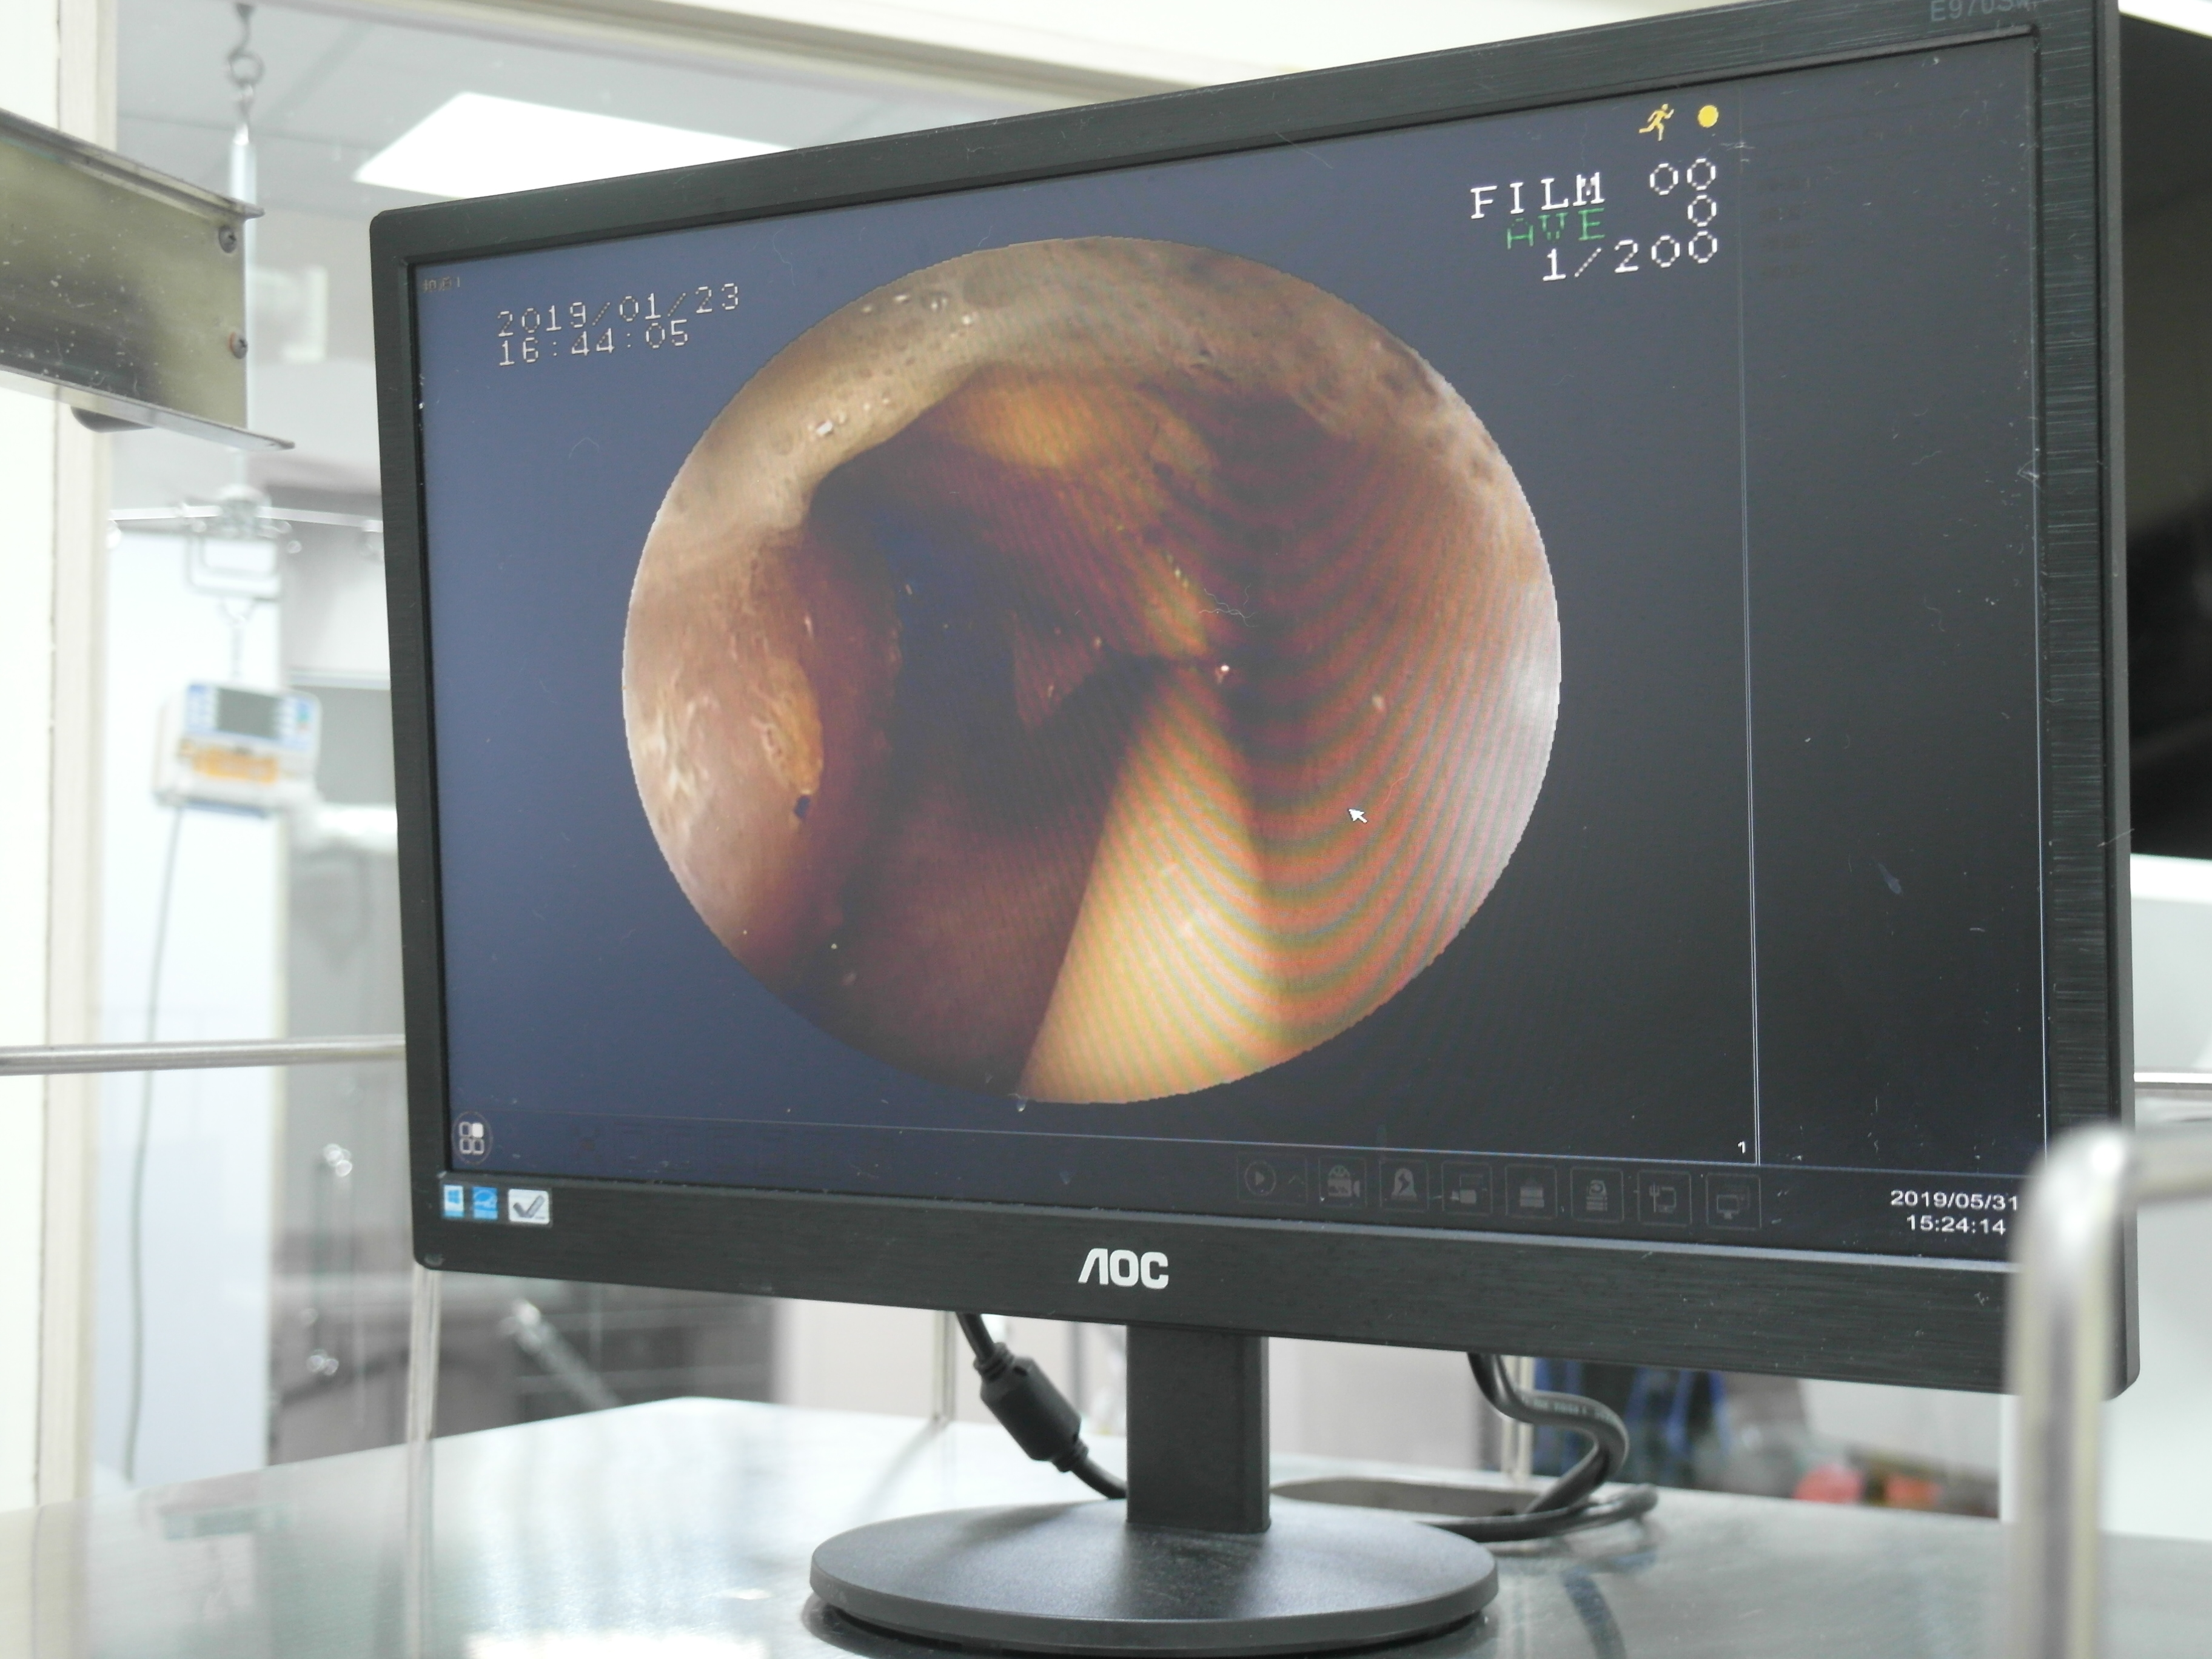

胃食道異物夾取手術精選輯 圖多慎入 首頁 病例分享 內視鏡微創治療 胃食道異物夾取手術精選輯 圖多慎入 傳統食道異物、胃異物都必須手術切開身體後把異物取出,可能會有手術的併發症、術後疼痛、需要住院、傷口照護的問題。 使用無創內視鏡 直接夾取異物,身體沒有任何創口、術後沒有傷口需要照護、也沒有手術造成疼痛感,也可以避免需要居家照護傷口的麻煩事。 **但有些狀況仍必須傳統切開手術喔** 本院隨機分享異物病例及吃進去的東西 襪子 ---- 髮圈 ---- 小豬玩具 ---- 雞骨頭 ----